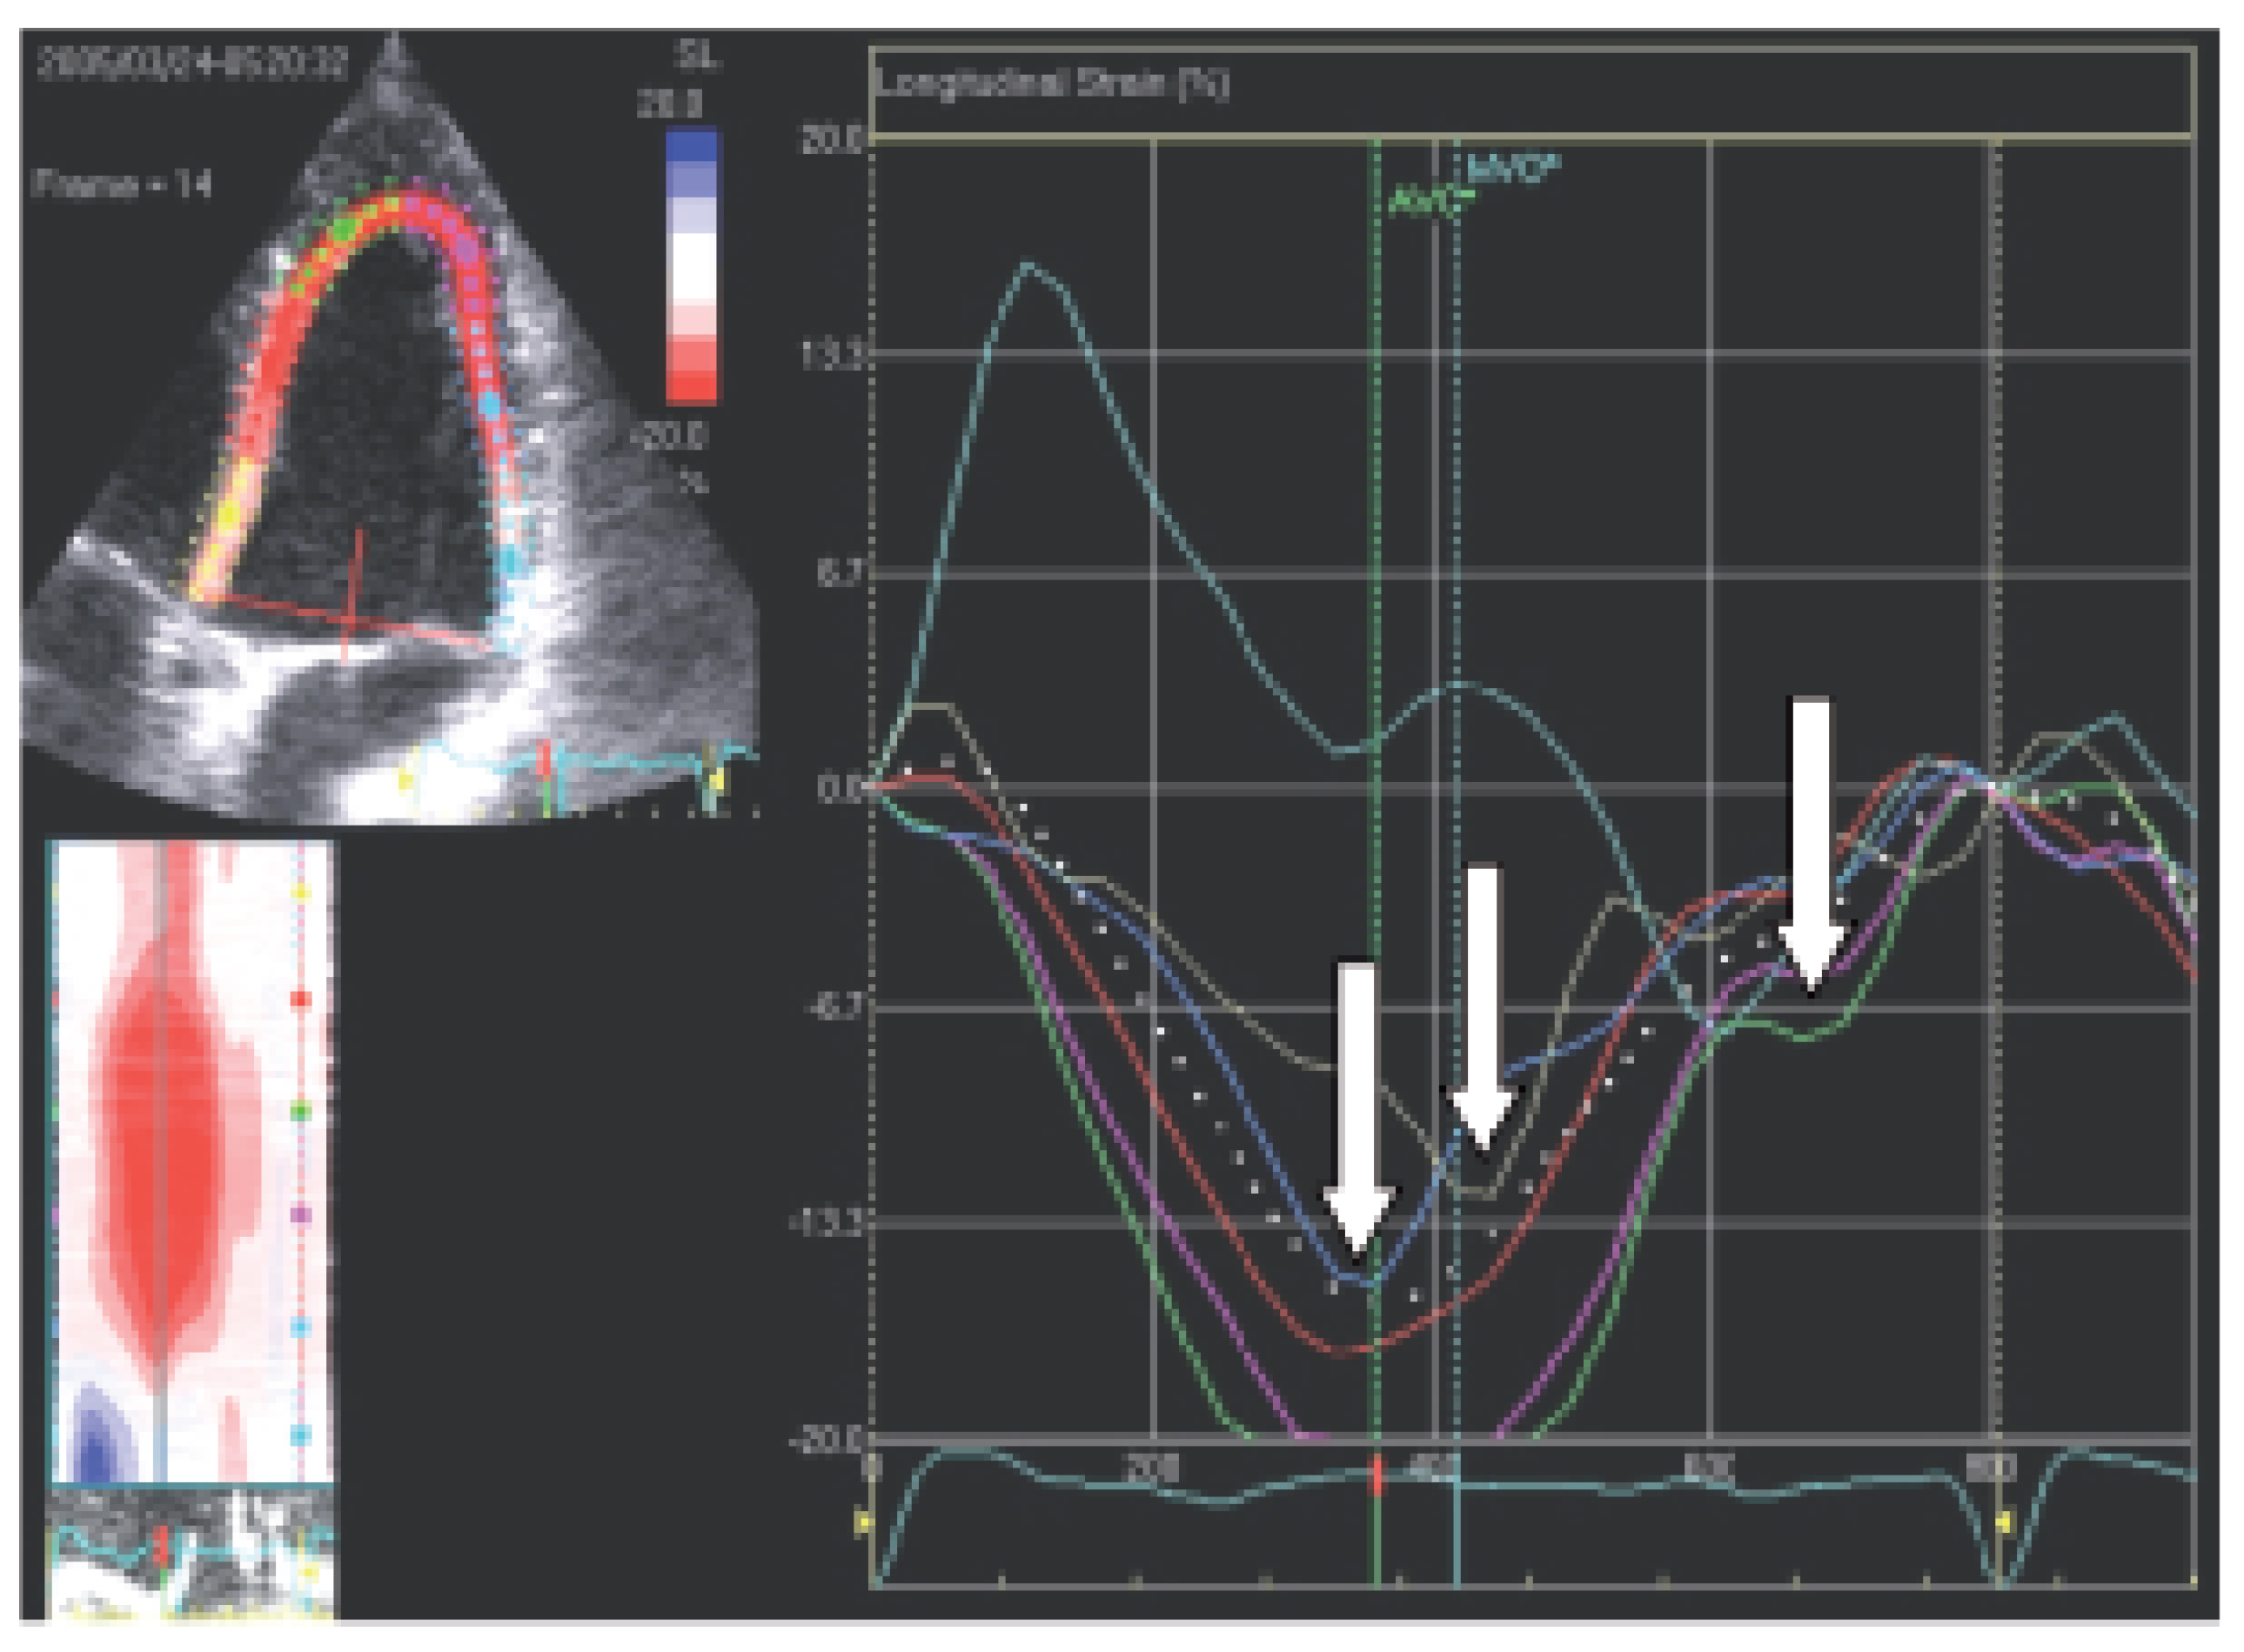

Gewebedoppler-Echokardiographie